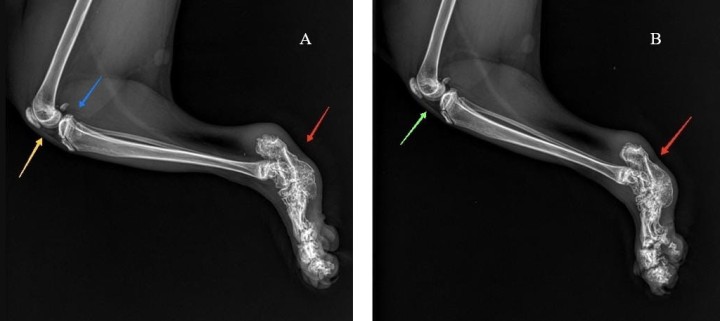

Se realizaron radiografías de ambas extremidades posteriores en proyección mediolateral (Fig. 1).

<p>Radiografías de las extremidades posteriores de una gata scottish fold de 1 año de edad. (<strong>A</strong>) Proyección mediolateral de la rodilla, tibia, tarso, metatarso y falanges de la extremidad posterior izquierda. (<strong>B</strong>) Proyección mediolateral de la rodilla, tibia, tarso, metatarso y falanges de la extremidad posterior derecha.</p>

Radiografías de las extremidades posteriores de una gata scottish fold de 1 año de edad. (A) Proyección mediolateral de la rodilla, tibia, tarso, metatarso y falanges de la extremidad posterior izquierda. (B) Proyección mediolateral de la rodilla, tibia, tarso, metatarso y falanges de la extremidad posterior derecha.

En ambas extremidades posteriores se evidencia un desarrollo anormal, con acortamiento, engrosamiento y deformidad de huesos y articulaciones, con pérdida del espacio articular a nivel del tarso, metatarso y falanges, con cambios degenerativos secundarios (signos de osteoartritis) y la presencia de una gran exostosis tarsal caudal, siendo estas lesiones las más evidentes a nivel radiográfico (Fig. 2). Además, se observa una leve efusión articular en rodilla izquierda (cambios en el paquete adiposo infrapatelar) con disminución del área radiolúcida y aumento de densidad correspondiente a la grasa infrapatelar, con desplazamiento caudal de la línea de la fascia poplítea (Fig. 2). En la rodilla derecha no se aprecian cambios compatibles con efusión articular.

<p>Mismas imágenes que la Figura 1. En ambas imágenes se observa un desarrollo anormal, con acortamiento y deformidad de huesos y articulaciones en tarso, metatarso y falanges, produciendo una pérdida del espacio articular intertarsal con una gran exostosis y crecimiento osteofítico de bordes irregulares a nivel de tarso (flecha roja). En la rodilla izquierda (<strong>A</strong>) se observa efusión articular (flecha amarilla) y desplazamiento caudal de la fascia poplítea (flecha azul). En la rodilla derecha (<strong>B</strong>) no existe efusión articular en la rodilla, visualizándose correctamente el cojinete adiposo infrapatelar (flecha verde).</p>

Mismas imágenes que la Figura 1. En ambas imágenes se observa un desarrollo anormal, con acortamiento y deformidad de huesos y articulaciones en tarso, metatarso y falanges, produciendo una pérdida del espacio articular intertarsal con una gran exostosis y crecimiento osteofítico de bordes irregulares a nivel de tarso (flecha roja). En la rodilla izquierda (A) se observa efusión articular (flecha amarilla) y desplazamiento caudal de la fascia poplítea (flecha azul). En la rodilla derecha (B) no existe efusión articular en la rodilla, visualizándose correctamente el cojinete adiposo infrapatelar (flecha verde).